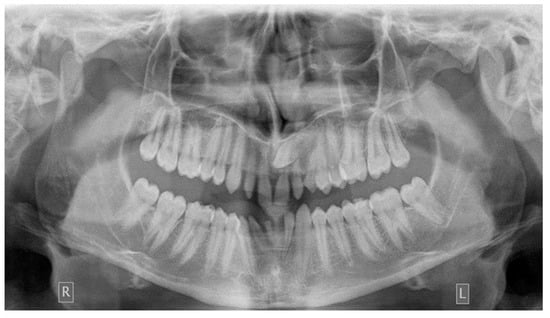

As far as the etiology of impaction is concerned, 205 patients presented one factor responsible for impaction, while 7 presented two. Table 2 shows the ectopic eruption path as the most frequent factor that was reported in 5.29% of total patients examined and mostly reported in maxillary canines. The next most common etiology was the loss of space in the arch (2.50%), followed by the ankylosis of deciduous teeth (1.71%). Concerning the rest of the causative factors, supernumerary teeth other than deciduous were observed in 1.29% of the patients, while the mesiodens was the most frequent supernumerary permanent tooth. In total, 1.21% of the sample presented tumors such as odontoma and osteoma, more often in association with maxillary central incisors. Supernumerary deciduous teeth affected 0.86% of the patients examined, while the ankylosis of permanent teeth was presented in 0.79 of the cases. The maxillary second premolars were the most frequently impacted teeth due to ankylosis. The least common etiology of impaction proved to be the primary failure of eruption, with 3 reported cases out of 212 patients, that following the radiographic examination were all confirmed by genetic tests. Panoramic radiographs indicated for some local etiological factors are presented below (Figure 1, Figure 2, Figure 3 and Figure 4).

Concerning the etiology of impaction, ectopic eruption path was our study’s most frequent local etiological factor. Maxillary canine was the most affected tooth, justified also by the results of previous studies [23,24]. The second most common etiologic factor was the loss of space in the arch, followed by the ankylosis of deciduous teeth and supernumerary permanent teeth. The least common cause of impaction proved to be the primary failure of eruption, which was present in the 0.21% of the total sample of panoramic radiographs.

Figure 3. Ectopic eruption of upper left canine.